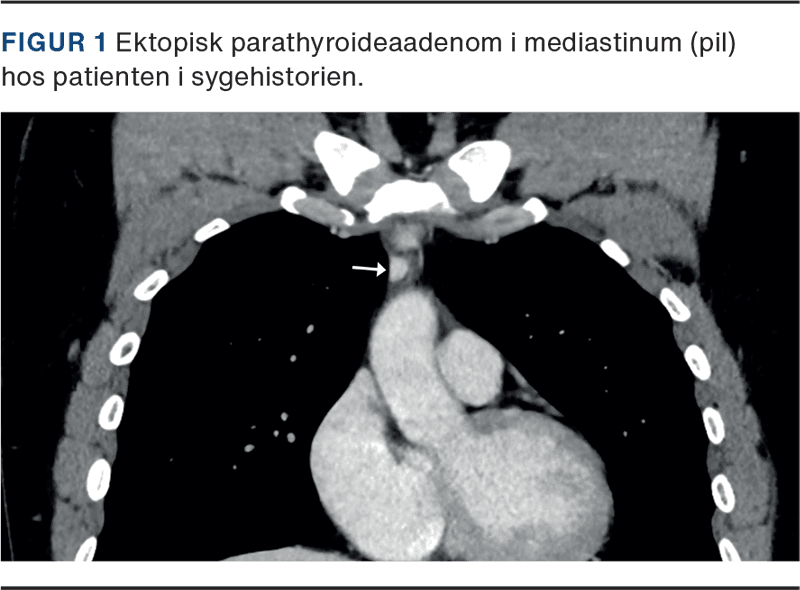

Efterfølgende havde patienten vedvarende hyperkalcæmi ([Ca2+] = 1,47 mmol/l) og forhøjet [PTH] (22,7 pmol/l) samt recidiv af nyresten. Han flyttede til en anden region, og på en tværfaglig konference besluttede man at foretage en dual-isotope (99mTc-sestamibi og 123I)-parathyroideascintigrafi med subtraktions-SPECT-CT, som kun viste et fokus i mediastinum (Figur 1) med let øget sestamibioptag, ikke oplagt foreneligt med parathyroideaadenom. Derfor besluttedes det at lave en diagnostisk CT med kontrast, der i første omgang beskrev en grænseforstørret lymfeknude i thorax. Skanningerne konfereredes herefter direkte mellem en nuklearmediciner og en radiolog, som enedes om, at der måtte være tale om et parathyroideaadenom i thymus. Samtidig kontrastopladning på diagnostisk CT og sestamibioptag på scintigrafi talte herfor. Patienten blev grundet lokalisationen opereret i thoraxkirurgisk regi i september 2023 med videoassisteret skopisk fjernelse af en tumor på 1 cm i højre thymushorn i mediastinum. Histologi viste parathyroideaadenom, og patientens kalkstofskifte normaliseredes derefter.

Ektopisk beliggende parathyroideaadenomer (EPA) kan være en udfordring at visualisere med billeddiagnostik. Prævalensen af EPA er anslået til omkring 20% i ikkeopererede patienter med PHPT, men op til 66% i reopererede patienter [5]. I tvivlstilfælde kan man supplere parathyroideascintigrafien med diagnostisk CT med kontrast. Kontrastopladning på CT er typisk for parathyroideaadenomer. Vores case afspejler den diagnostiske betydning af supplerende CT med kontrast og det nyttige i tæt samarbejde mellem flere specialer i søgningen efter EPA.